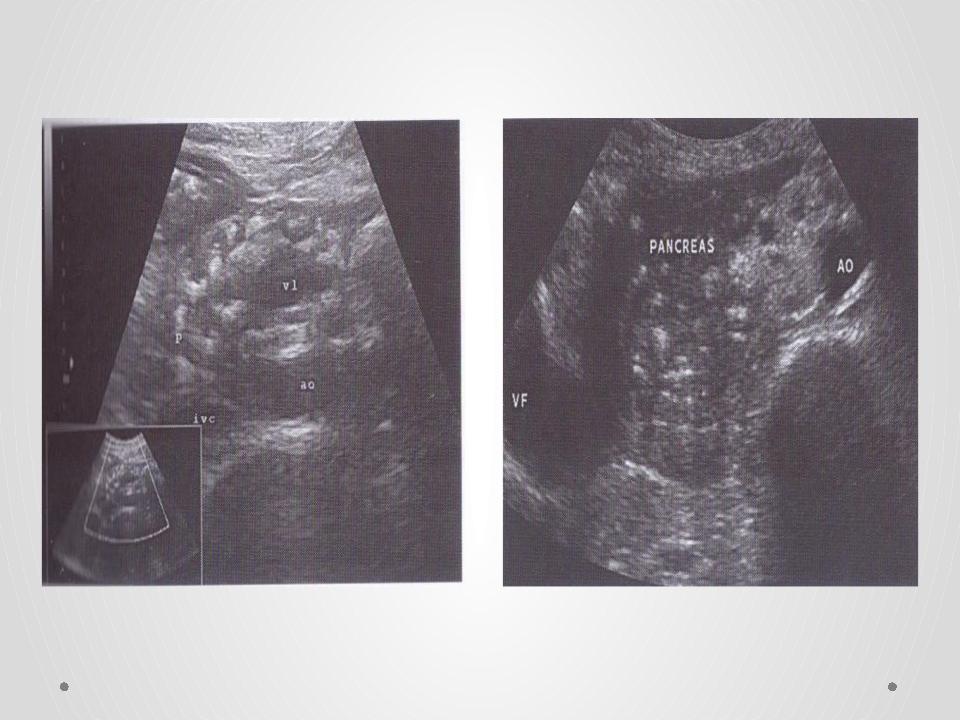

Фотографии и изображения, связанные с симптомами первичного склерозирующего холангита